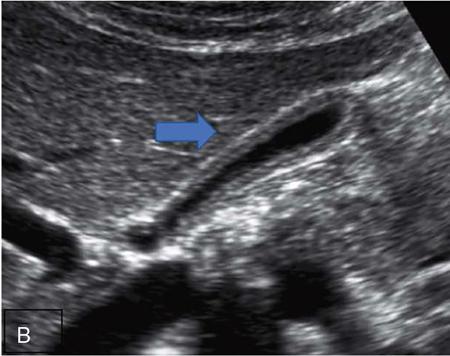

CROSS SECTIONAL ANATOMY OF ABDOMEN Satya Jha NORMAL ANATOMY OF ABDOMEN AND PELVIS Amandeep Singh The two major surfaces: The anterior and posterior layers of the coronary ligament converge on bare area (not covered by peritoneum). Its right and left margins form the right and left triangular ligaments. The right triangular ligament extends toward the diaphragm and separates right subphrenic space from right subhepatic space. The left triangular ligament gives tracts extending to the diaphragm and falciform ligament and does not compartmentalize the left subphrenic space. Ligamentum teres or the obliterated umblical vein is contained in falciform ligament which attaches the liver to anterior abdominal wall. The main portal vein, the proper hepatic artery and the common bile duct are contained within investing peritoneal folds of hepatoduodenal ligament at the porta hepatis (Fig. 7.2.2.1). Liver is divided into eight segments which are functionally independent and have their own vascular supply and biliary drainage. Arterial circulation: The branches of the hepatic artery accompanying the portal veins. Hepatic venous system: The right, middle, and left hepatic veins draining into IVC (Figs. 7.2.2.2 and 7.2.2.3). The gallbladder is a blind pear-shaped muscular membranous sac which is an embryologic derivative of the foregut, is a pouch lying along the undersurface of the liver. The gallbladder fossa is located in the plane of the interlobar fissure, which lies between the right and left hepatic lobes. Its major function is to store and concentrate bile which is produced by the liver. It measures approximately 4 cm in diameter when it is normally distended. Gallbladder is a smaller tubular structure in contracted state. The normal gallbladder wall thickness ranges from 1 to 3 mm. The gallbladder is divided into the fundus, body and neck. Infundibulum is present in the region of neck of the gallbladder, which is called the Hartmann pouch, where gallstones are usually impacted. Intrahepatic biliary radicles (IHBRs) scattered throughout the liver get confluent towards the hilum. They unite to form the right and left main hepatic ducts which further unite to form common hepatic duct (CHD) at the hilum. Common bile duct is formed by the union of cystic duct with common hepatic duct. The main pancreatic duct is joined with the common bile duct to form the ampulla of Vater at the major duodenal papilla (Figs. 7.2.2.4 and 7.2.2.5). Pancreas is located in anterior pararenal space of retroperitoneum anterior to perirenal (Gerota’s) fascia and posterior to parietal peritoneum. It is divided into head, uncinate process, neck, body and tail from right to left. Pancreas lies anterior to portal vein, which marks the point of transition between the body and neck. The region between head of pancreas and second and third parts of duodenum is known as the pancreatic groove. In postnephrectomy cases or with agenesis of kidney or ectopic kidney, pancreas moves posteriorly to partially fill in the empty renal fossa; its soft tissue density should not be mistaken for recurrent tumour. It is located in the pancreatic groove and is bounded superiorly by the duodenal bulb, laterally by second portion of duodenum, inferiorly by third portion of duodenum, medially by superior mesenteric vein and anterior to inferior vena cava. It is a wedge or wedge shaped lying posterior to superior mesenteric artery and vein. It is an imaginary junction between the head and body and lies directly over the junction of the splenic vein and superior mesenteric vein. It is located posterior to the lesser sac and anterior to the aorta, left adrenal gland, left kidney, and renal vessels and runs obliquely upward to the left of the superior mesenteric vessels. It is situated median to the colonic flexure and anterior to the left kidney. It is located in close proximity to the splenic hilum without a notable relation with the body of pancreas. It is seen anterior to the left kidney and median to the colonic flexure. The distal part of the tail passes between the peritoneal layers of the splenorenal ligament (Fig. 7.2.2.6 and 7.2.2.7).